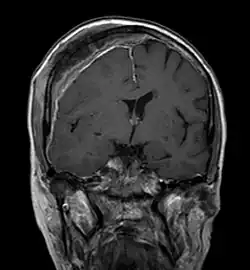

Les fractures de compression d'un ou plusieurs corps vertébraux peuvent conduire à une compression médullaire ou à un syndrome de la queue de cheval et sont des complications redoutées d'une métastase osseuse dans une vertèbre[80]. Les syndromes de compression médullaire se traduisent la plupart du temps par de fortes douleurs dorsales, ainsi que des insuffisances motrices et sensitives des extrémités inférieures. Le contrôle de la vessie et du rectum peuvent aussi être détériorés par la compression médullaire.

Chez environ 5 % de tous les patients du cancer apparaît une compression médullaire[81]. La proportion approximative des vertèbres atteintes est de 70 % dans le domaine des vertèbres thoraciques, de 20 % dans celui des vertèbres lombaires et de 10 % dans celui des vertèbres cervicales[80]. Dans 4 à 22 % des cas de compression médullaire, c'est le premier symptôme du cancer primitif. Ceci est en particulier le cas pour les lymphomes, les carcinomes du rein et des bronches[82].

Le temps de survie moyen des patients avec une compression médullaire causée par des métastases osseuses est d'environ 2 à 6 mois[81],[83],[84].

L'intervalle entre la survenue d'épisodes neurologiques et leur traitement ne devrait pas dépasser 24 heures. Le traitement est purement palliatif, par exemple par radiothérapie, de hautes doses de glucocorticoïdes comme la dexaméthasone et l'ostéosynthèse avec implants[80],[81].